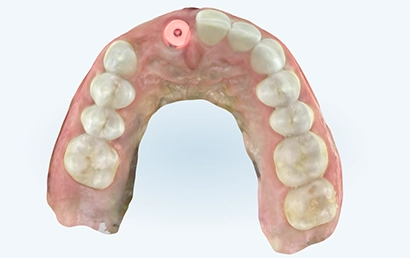

iTero scan taken immediately after implant placement.

Clinically made custom abutment

Appointment #4: Custom healing abutment placement appointment

The existing healing abutment was removed, and a lab-designed custom healing abutment was installed. It allowed us to shape the emergence profile and ensure the best gingival aesthetics.

Lab-designed custom abutment

Abutment seating confirmation

Appointment #5: Scanning for the final restoration

The custom healing abutment was removed, and an emergence profile was scanned with the iTero™ intraoral scanner. A subsequent scan with the scan body in place was conducted. Photos were taken, attached to the iTero™ Rx form, and sent to the lab.

Emergence profile scan

Scan body scan

The fixed cantilever bridge was inserted, and seating was verified with a periapical X-ray. Torqued to 20 Ncm. Contacts were checked, and occlusion was adjusted. Final photographs and a scan were taken for the records.

Images were taken at the insertion appointment. Soft tissue healing remains ongoing.